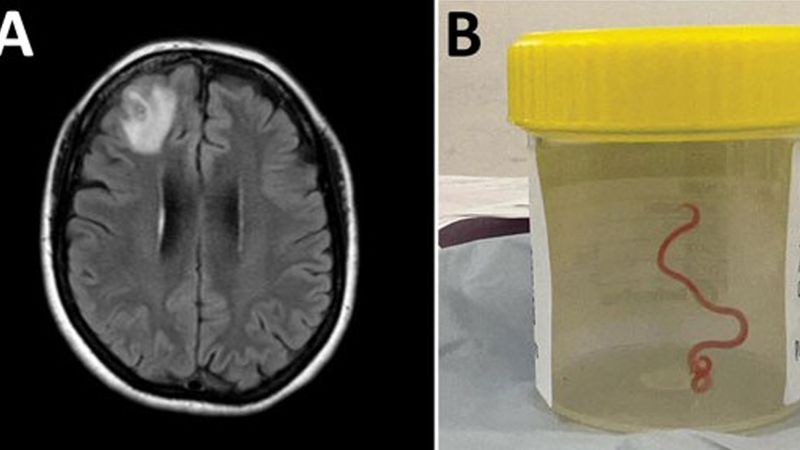

A 52-year-old man in the US developed tapeworm larva in his brain, likely from consuming undercooked bacon, leading to neurocysticercosis. Despite no recent travel to endemic areas or contact with pigs, the man's habit of eating undercooked bacon and poor hand hygiene likely caused the infection. The case highlights the increasing frequency of such infections in developed countries and the importance of considering neurocysticercosis in evaluating acute changes in migraines.